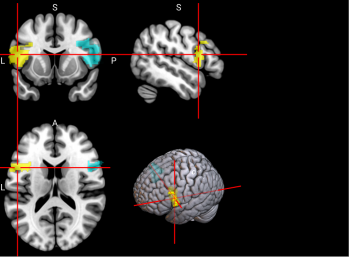

/word/media/image13.png/word/media/image13.png

65,

66

L & R Inferior parietal gyrus, excluding supramarginal and angular gyri (IPG)

The inferior parietal gyrus is involved in attentional, semantic, and social cognitive functioning [65].

/word/media/image14.png/word/media/image14.png